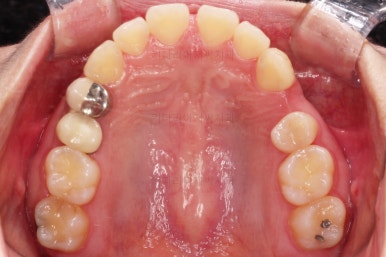

초진 시 입안의 모습을 보실게요.

이번 환자분의 경우는 치아 결손 부위의 잇몸뼈도 양호했고 공간도 그리 크진 않았으며 윗니는 갯수가 1개 부족해도 교합을 맞추는데 문제가 거의 없기 때문에 시간이 좀 더 들더라도 임플란트 없이 앞니 사이 틈과 결손부위 틈새를 모아보기로 했어요.

우선 장치를 부착했습니다.

이번에 선택한 장치는 엠파워 클리어라고 하는 자가결찰 세라믹 장치인데요.

흔히 아시는 클리피씨 장치와 같은 분류의 장치입니다. 클리피는 일본, 엠파워는 미국 제조사라는 차이가 있지만 큰 틀에서는 세라믹 바디에 금속 클립이 달린 거의 동일한 장치라고 보시면 됩니다.